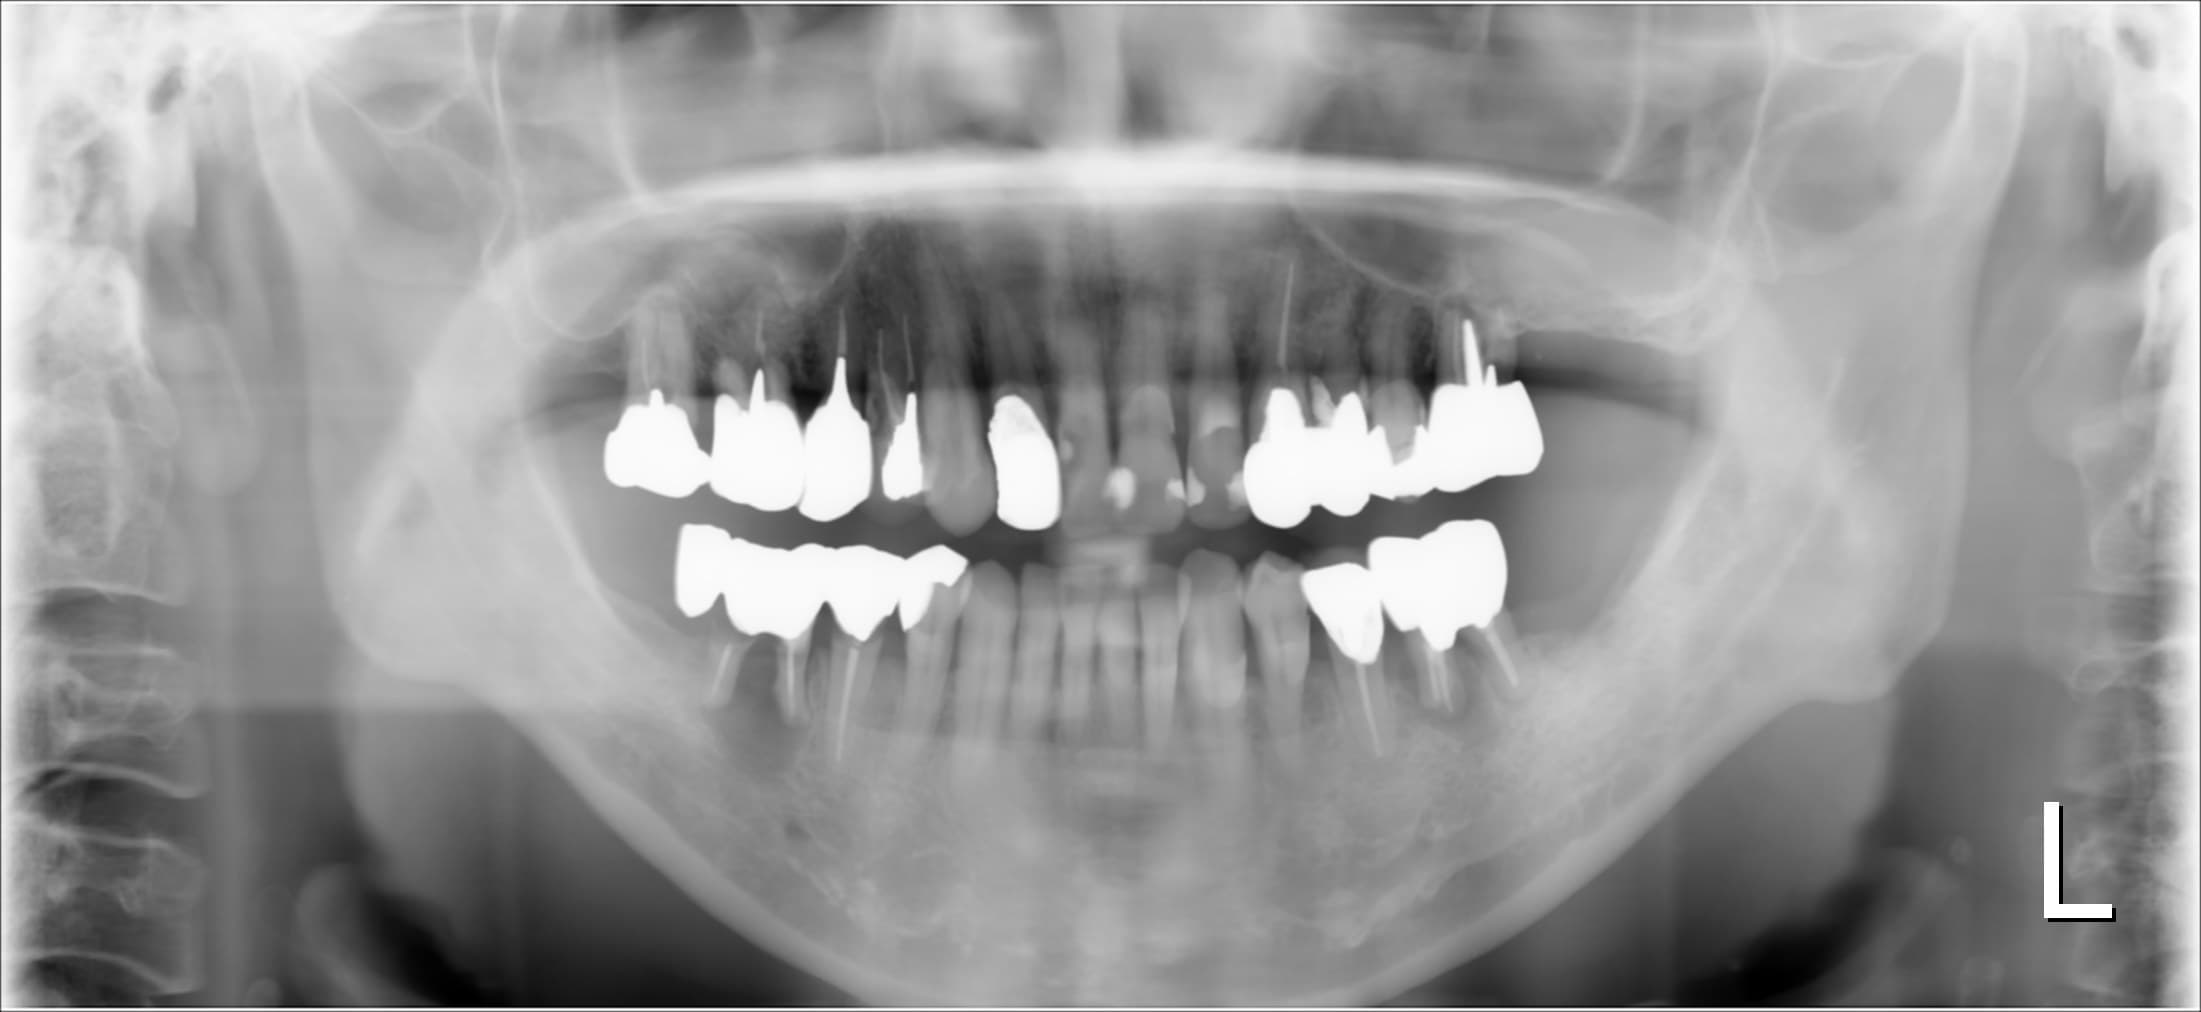

今回ご紹介するのは、長年虫歯の治療で苦労されてきた50代女性の方です。

(歯周専門治療が終了してこれから院長と虫歯の治療を行く予定です)

歯磨きはかなり気を付けて欠かさず歯間ブラシも使っている。歯磨き粉もフッ素入り。定期健診で悪い所があれば、直ぐに治療をしてきた。

なのに、

虫歯の治療が次から次へと必要になる。

この方もそんな一人でした。